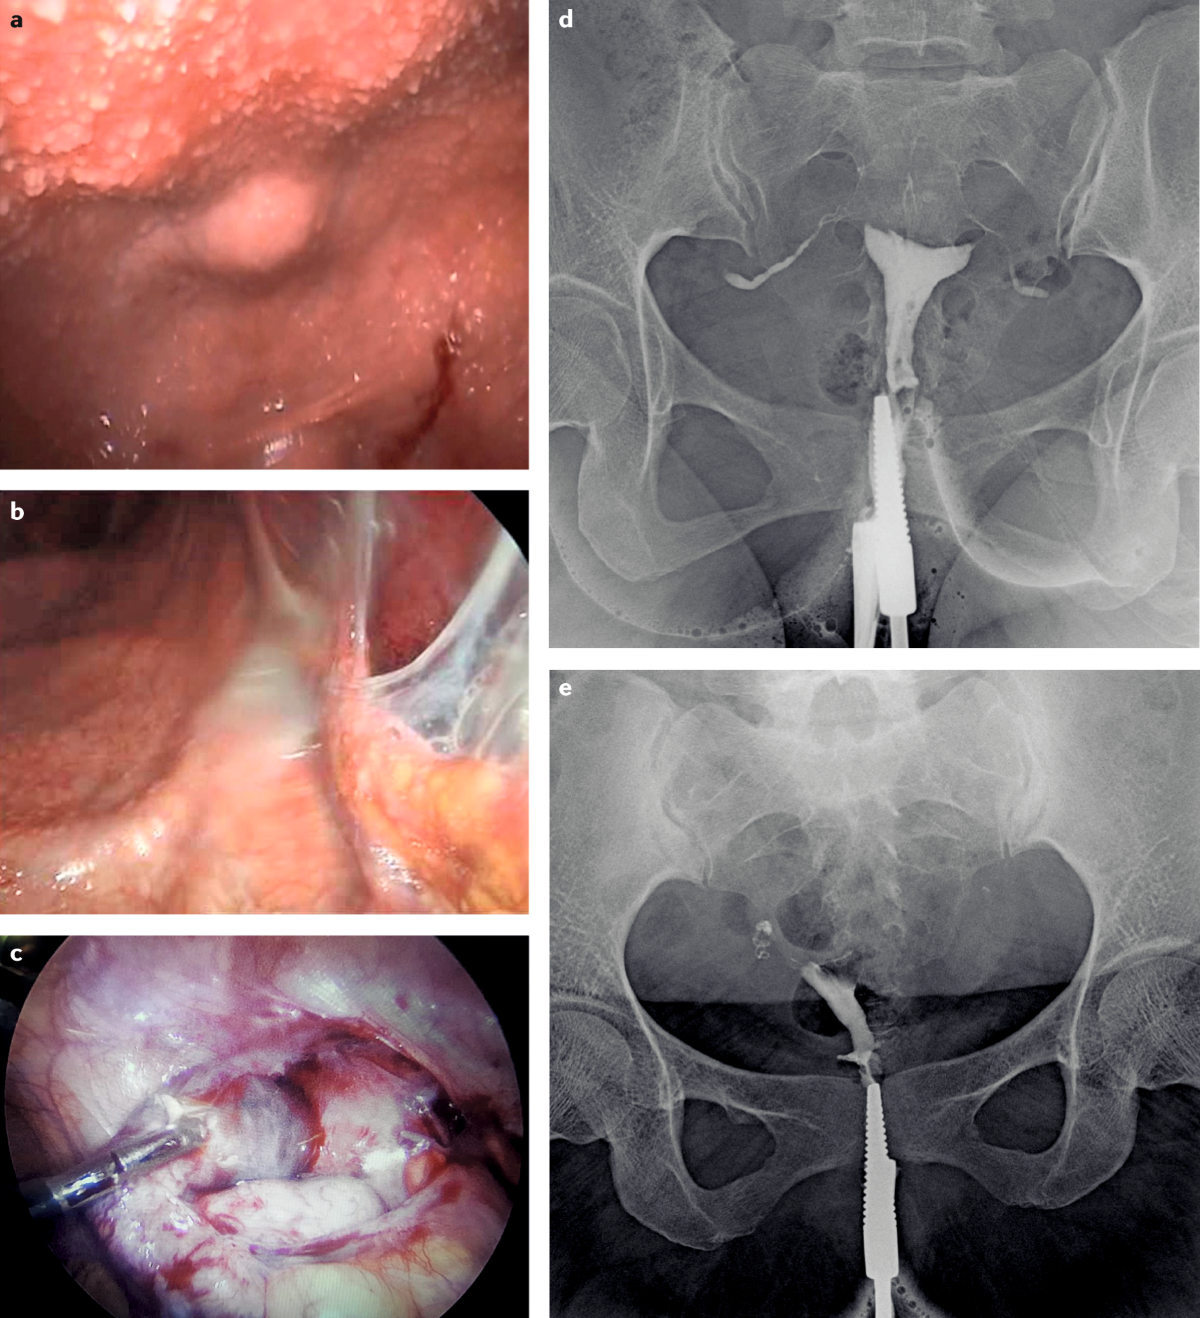

Urogenital tuberculosis — epidemiology, pathogenesis and clinical features | Nature Reviews Urology